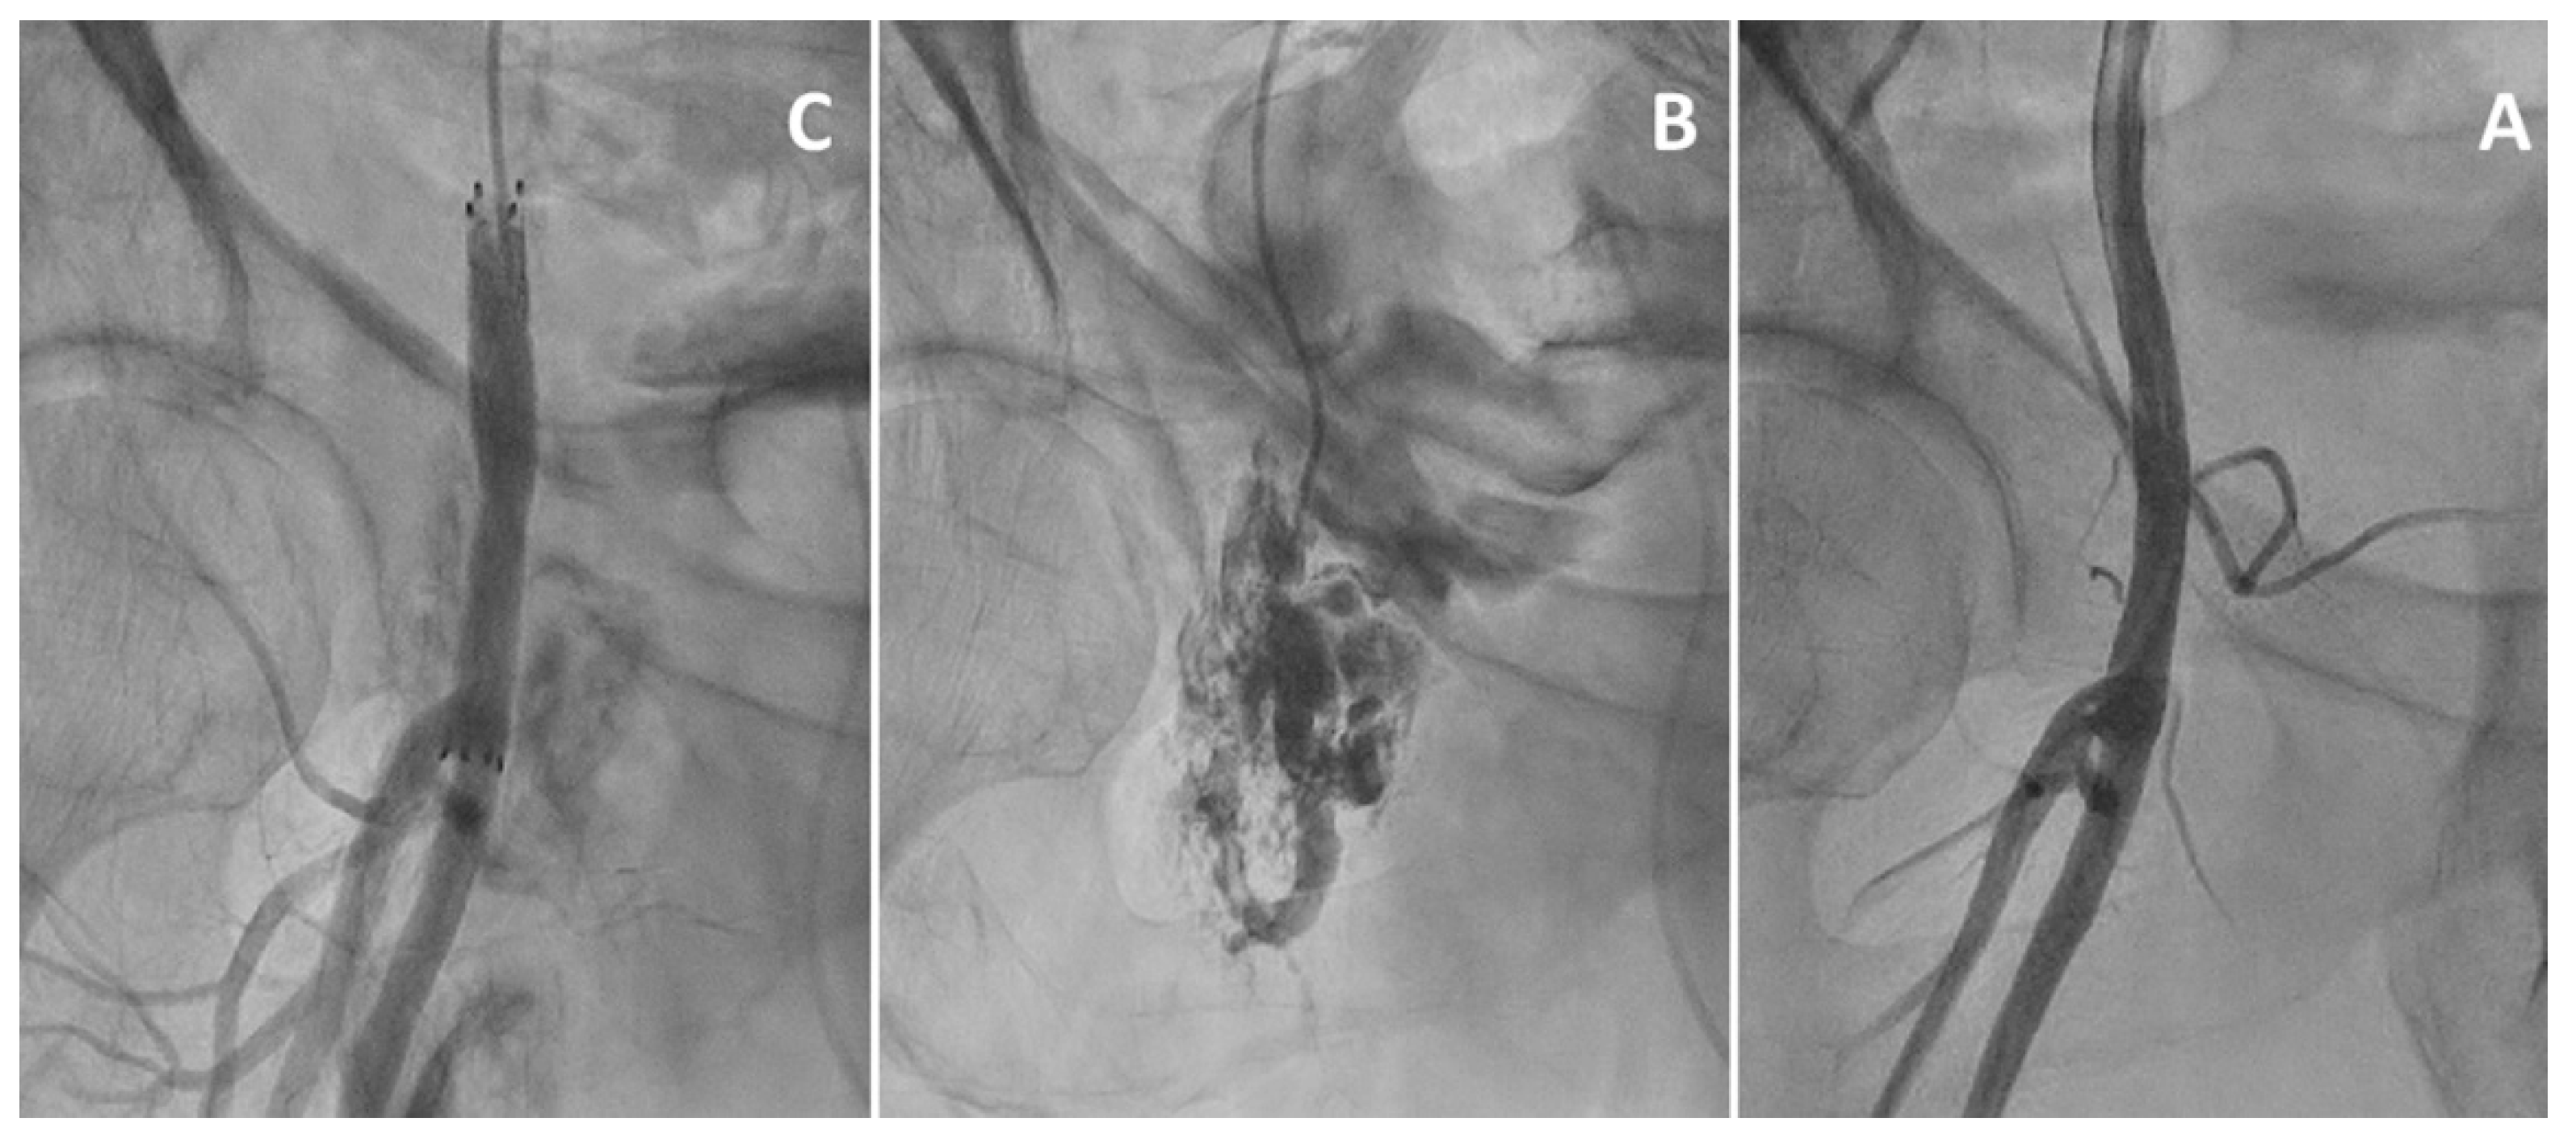

- Sedaghat, A.; Neumann, N.; Schahab, N.; Sinning, J.-M.; Hammerstingl, C.; Pingel, S.; Schaefer, C.; Mellert, F.; Schiller, W.; Welz, A.; et al. Routine Endovascular Treatment with a Stent Graft for Access-Site and Access-Related Vascular Injury in Transfemoral Transcatheter Aortic Valve Implantation. Circ. Cardiovasc. Interv. 2016, 9, e003834. [Google Scholar] [CrossRef] [Green Version]

- Sedaghat, A.; Hansen, K.L.; Schahab, N.; May, M.C.; Weber, M.; Stundl, A.; Shamekhi, J.; Schaefer, C.; Nickenig, G.; Sinning, J.-M.; et al. Long-term follow-up after stent graft placement for access-site and access-related vascular injury during TAVI—The Bonn-Copenhagen experience. Int. J. Cardiol. 2019, 281, 42–46. [Google Scholar] [CrossRef]

- De Backer, O.; Arnous, S.; Sandholt, B.; Brooks, M.; Biasco, L.; Franzen, O.; Søndergaard, L. Safety and efficacy of using the Viabahn endoprosthesis for percutaneous treatment of vascular access complications after transfemoral aortic valve implantation. Am. J. Cardiol. 2015, 115, 1123–1129. [Google Scholar] [CrossRef]